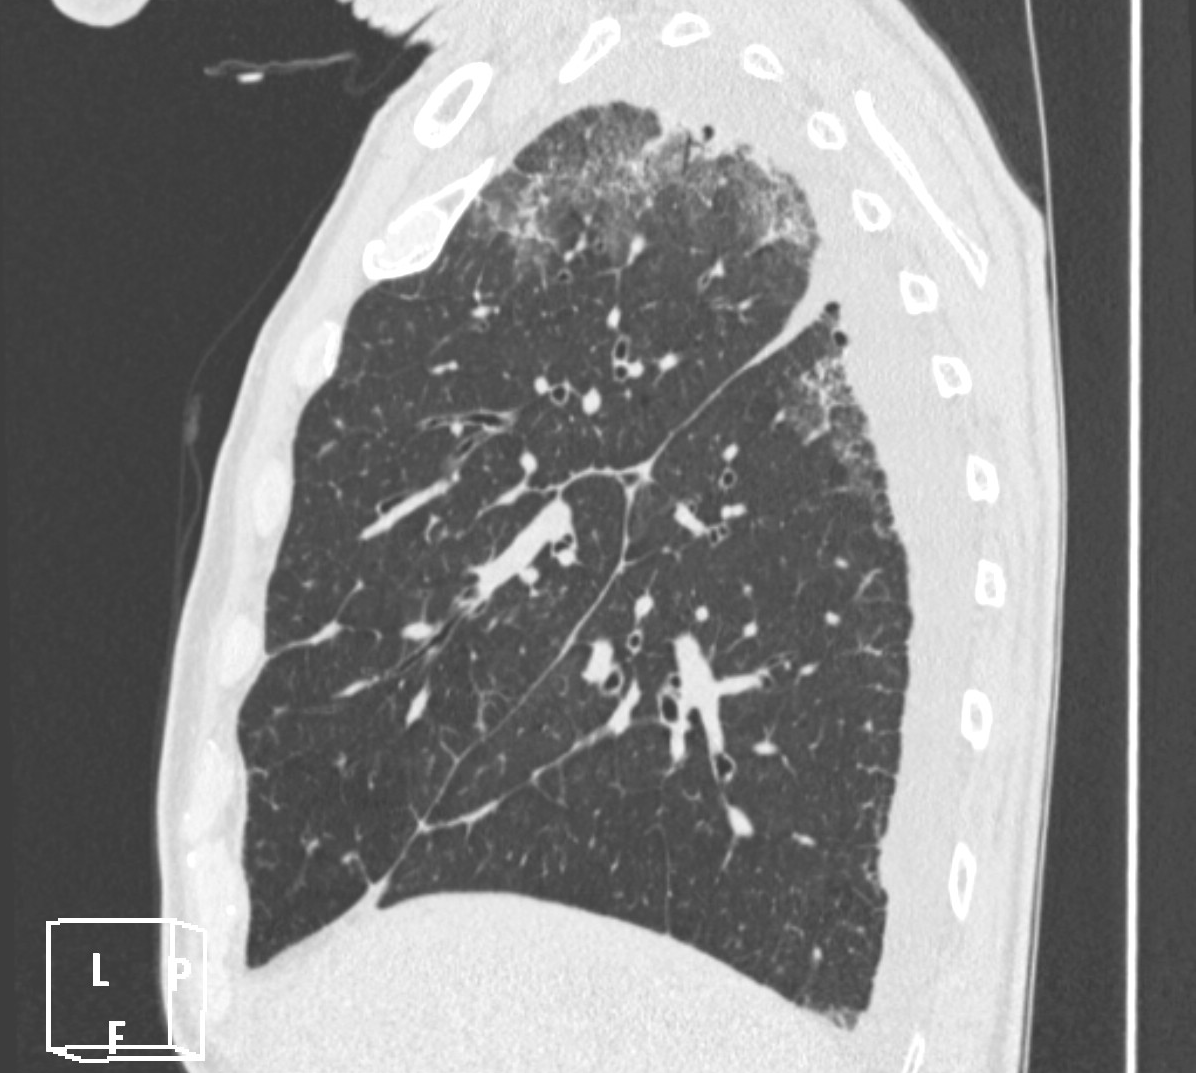

4: Miliary pattern: sarcoidosis, CT, lung window. Axial image and sagittal reformat.

A 67 year old female suffering from COPD. Bilateral rough branching interstitial widening and patchy, miliary nodules with perihilar dominance along the bronchovascular fibres and the fissures.